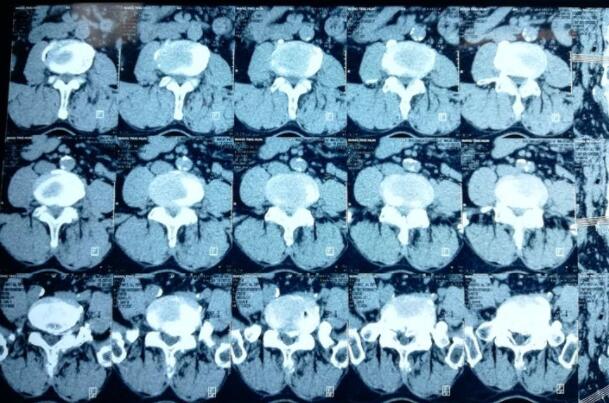

据外国文献报道,在一般成年人中,通过常规X 线检查检出钙化的发病率为5%~6%,随着年龄的增长,85 岁以上患者的发病率近45%。Chanchairujira 等通过223例尸检获取的数据发现椎间盘钙化在老年人中很常见(约13%),并且钙化最易发生在纤维环内(约63%),其次发生在髓核内,同时钙化的发生率与年龄的增大和椎间高度的丢失程度呈正相关,作者认为椎间盘钙化的主要相关因素为年龄,而非全身性疾病。然而,Aessopos 等的研究发现,地中海贫血患者椎间盘钙化发病率为23.33%, 明显高于普通患者,这可能与地中海贫血导致的机体广泛骨骼代谢异常增高有关。不同的研究方法得出的发病率数据不同,一方面,可能由于钙化往往伴随炎症,椎间盘局部钙化和炎症导致的临床症状和体征的相似性, 导致钙化被忽视,造成钙化的漏诊。另一方面,不同研究使用的钙化检测方法敏感性有较大差别,常规的X 线检查敏感度较低,只能发现较大的突出钙化,而组织形态学、扫描和透射电镜、免疫组化等检查能够检测到早期极细微的钙盐沉积,得到的数据更为精确。但这些方法需要手术进行标本的采集,标本制备要求高,并存在选择性偏倚,无法用于普查。

椎间盘钙化的成分 椎间盘钙化形成的过程非常复杂,涉及羟基磷灰石、焦磷酸钙、碱性磷酸钙和草酸钙等钙盐的沉积,钙化脱出物的X 射线衍射和电镜观察显示巨大的钙盐结晶存在于明显降解退变的细胞外基质中。通常认为椎间盘钙化的主要成分是羟基磷灰石,但也包括微量的其他钙盐结晶。